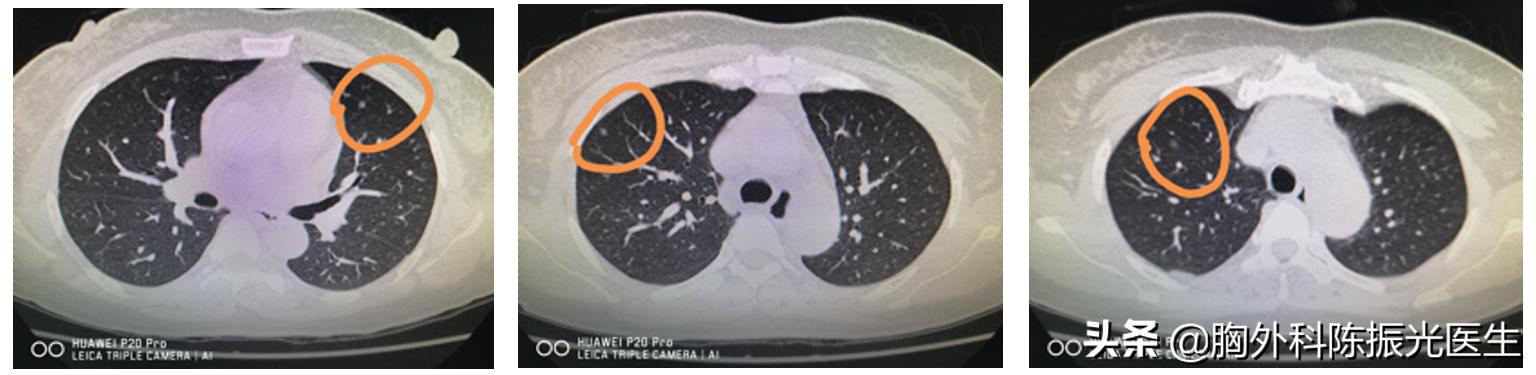

前几天门诊的时候,有位女士来找我,两个肺上长了好几个小结节,都是3到4厘米左右。我问家里有没有人吸烟啊,她回答说她没有吸烟,丈夫也没有这个习惯。然后又想了想问:“陈医生,我几乎每天都要艾灸1-2个小时,会不会和我长肺结节有关系啊?”

看她的几张CT影像,肺部小结节确实明显。